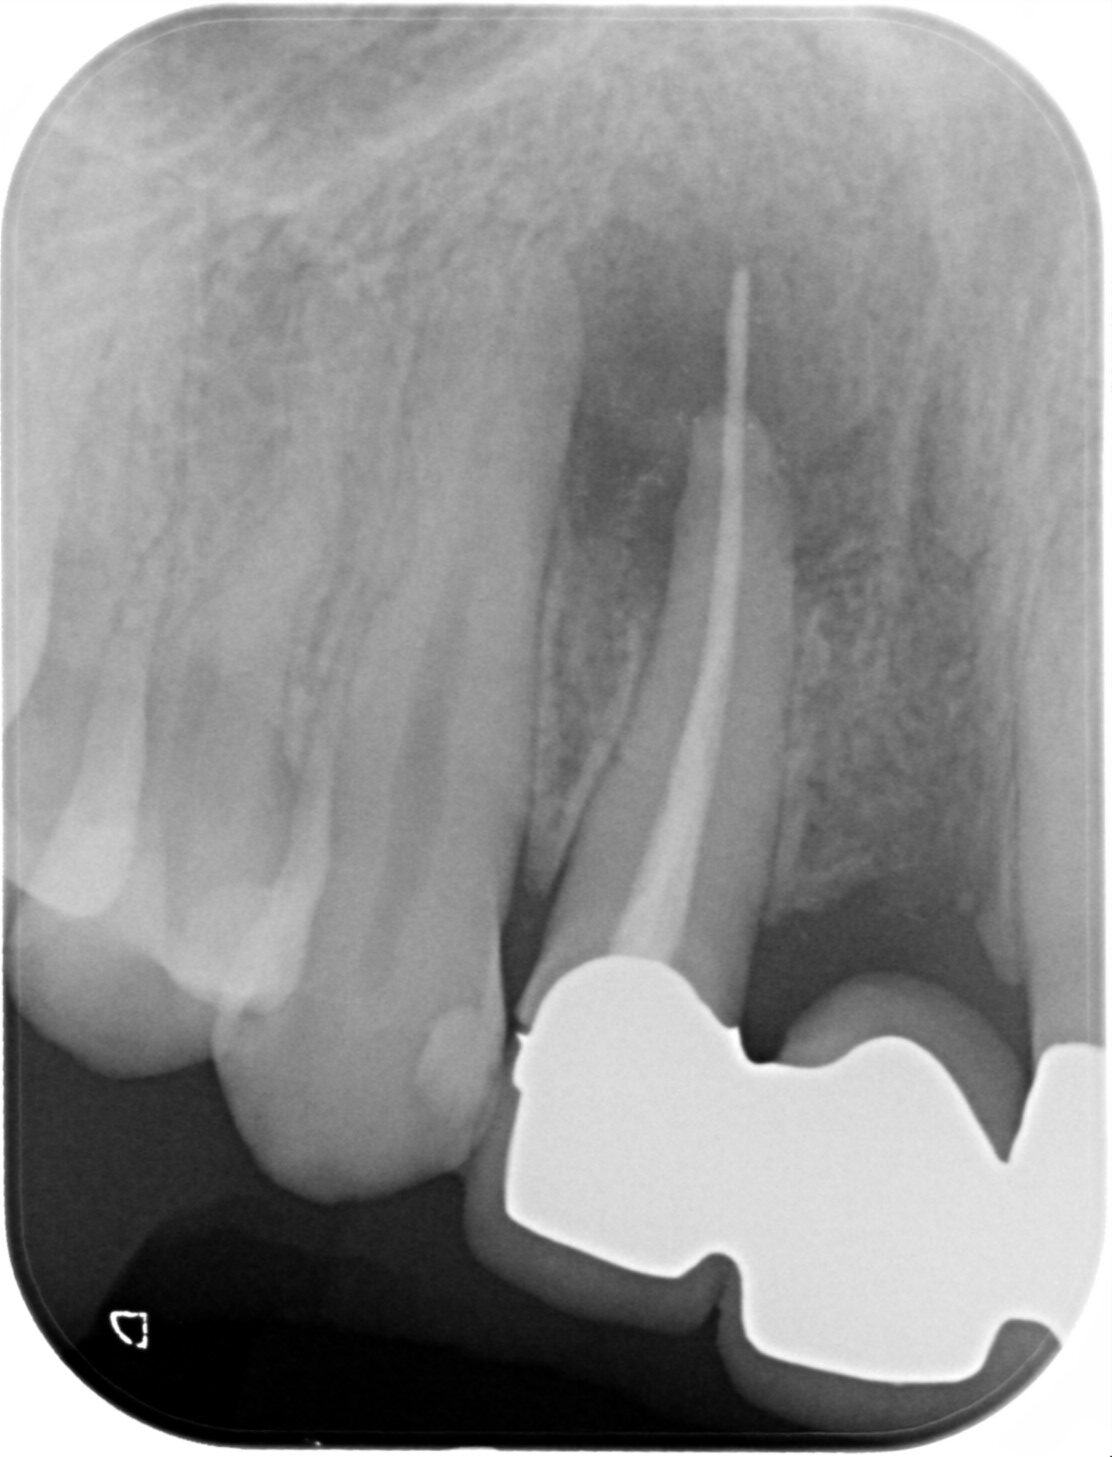

画像

2023.1/25 他院で被せ物を作成した歯が腫れて痛みがあるということでご来院。

2024.6/5 被せ物は外し、当院で改めて根っこの治療を行いました。

2024.9/5 右上2番の治療が終わり、ジルコニアクラウンの被せ物を作成しました。

治療部位 右上2番

費用 保険分+自費で約11万円

治療期間 21ヶ月